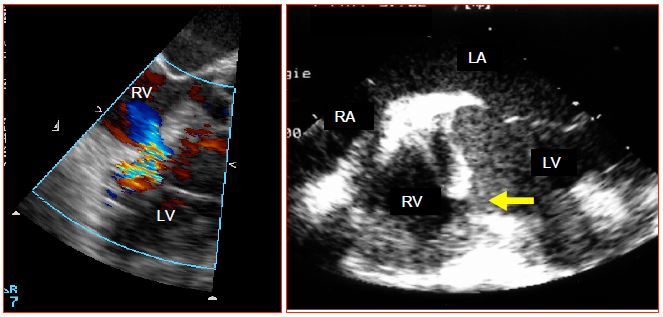

For further information, reference may be made to Chapter 14 (Paediatric cardiac surgery). Illustrations are taken from transesophageal echocardiography (TEE), which anaesthetists may perform in the operating theatre.